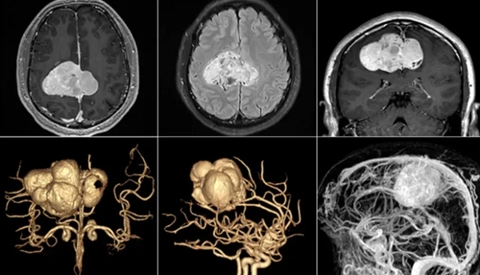

Bởi vì trường hợp của Tiểu Vương là một ca khó, anh được chuyển tới Khoa Phẫu thuật Thần kinh của Bệnh viện Liên minh trực thuộc Đại học Y Phúc Kiến (Trung Quốc). Tiến sĩ Lương Nhật Sinh - bác sĩ trực tiếp phẫu thuật cho anh cho biết: “Kiểm tra cộng hưởng từ xuyên sọ cho thấy có một khối u khổng lồ bên cạnh não liềm của bệnh nhân. Nó có hình dạng giống như một chiếc lá phong và có đường kính khoảng 7cm, tương đương với chiều rộng 4 ngón tay của người trưởng thành khi đặt sát nhau.

Hình ảnh khối u não khổng lồ của bệnh nhân được phát hiện nhờ dấu hiệu tê tay trái (Ảnh BV cung cấp)

Khối u ảnh hưởng đến vùng chức năng vận động của hai bên não và xoang dọc, cấu trúc tĩnh mạch lớn, trực tiếp chèn ép và tác động đến máu tĩnh mạch quay trở lại, khiến vùng vận động não phải của bệnh nhân bị rối loạn chức năng. Điều đó khiến bệnh nhân bị tê bì, yếu các chi bên trái, thậm chí là cả nửa thân trái.